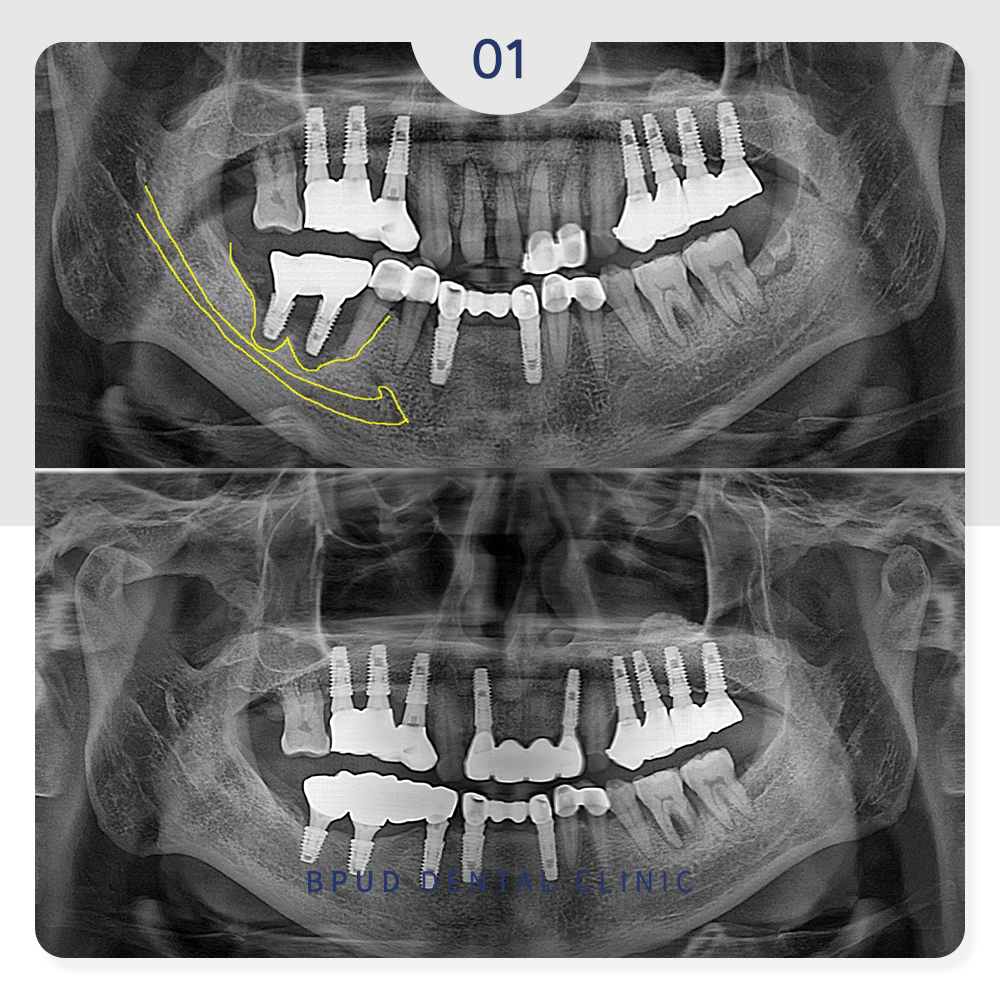

환자분의 처음 내원 당시 파노라마입니다.

임플란트를 하신 갯수는 많았지만

상대적으로 유지 관리가 잘 되어 있는

모습으로 꾸준한 관리를 말씀 드렸었는데요.

22.11.28

약 3년 뒤, 앞니 보철의 파절과

오른쪽 아래 잇몸이 불편하시다며

오랜 기간이 지나 내원해 주셨습니다.

임플란트 식립 후 오랫동안 관리가 되지 않아

심한 잇몸뼈의 흡수가 일어나 있음을 관찰할 수 있었는데요.

아래쪽의 신경관까지 골흡수가 일어나

재식립이 상당히 어려운 상황이었지만

기존 임플란트를 제거하고 치조골 이식을 통해

다 녹아버린 잇몸뼈를 재건하여 재식립 수술을

진행하기로 계획을 수립하였습니다.